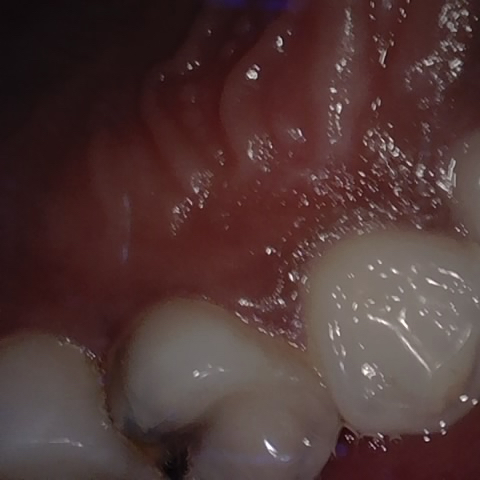

Annotated as "Good"